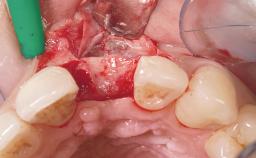

Late Placement of an Implant in a Maxillary Left Central Incisor Site

A 36-year-old female patient was referred for the replacement of the upper left central incisor (tooth 21), which had fractured. Although the tooth had been asymptomatic for many years, the crown began to loosen, at which time she presented to her dentist for an assessment. Teeth 21 and 22 had both been endodontically treated many years previously. She was a healthy individual and a non-smoker.

The crown of tooth 21 was splinted to the adjacent teeth with composite resin, and the gingiva was inflamed.

Bone Augmentation Horizontal|Staged

Augmentation Materials Xenogenous|Membrane

Soft Tissue Grafting Simultaneous

Bone Volume Deficient horizontally, requiring prior grafting